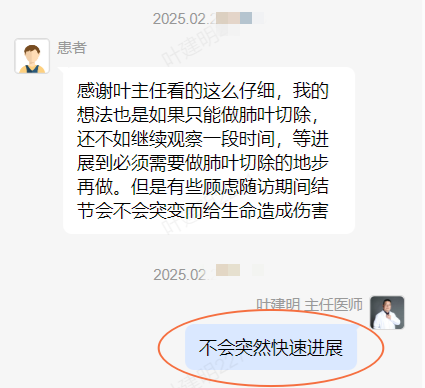

后续交流:

结友担心结节会短期内突然进展,我当时还告诉他不至于的:

我的想法是主病灶在右上叶,且多发,而且位置较深,若手术很可能要切且叶,虽考虑是肿瘤范畴的,但由于不管病灶A还是病灶B均仍是磨玻璃密度,没有纵隔窗可见的实性成分,在两肺多发病灶的情况下,适当保守点再随访下,待有进展并风险增高再干预也不至于影响预后。而且根据既往经验,磨玻璃密度的肺癌基本太会短时间内快速进展。